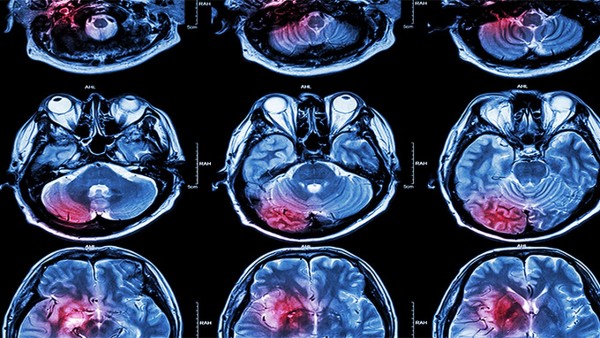

臨床前藥理試驗(yàn)表明,腦血栓片可減輕局部腦缺血大鼠腦壞死的重量,提高全腦缺血小鼠的抗缺氧能力,減少腦組織MDA的產(chǎn)生,減緩能量代謝,增加正常腦膜血流量,保護(hù)缺血心肌,延長缺氧存活時(shí)間,抑制體外血栓形成,具有抗凝作用。

現(xiàn)代中藥在治療腦梗死等慢性病方面具有長效性強(qiáng)、安全性高、耐藥性差等優(yōu)點(diǎn),但缺點(diǎn)是有效成分含量不穩(wěn)定,劑量大。腦血栓片的主要功能是促進(jìn)血液循環(huán),消除血瘀,清醒大腦,通絡(luò),潛陽,熄風(fēng)。用于血瘀、肝陽上亢等中風(fēng)先兆,如肢體麻木、頭暈、腦血栓形成中風(fēng)、口眼歪斜。偏癱等疾病。具有預(yù)防和治療效果。

腦血栓片主要用于治療早期中風(fēng)、頭痛、胸痹、積聚、閉經(jīng)等疾病。用于治療腦血栓形成、心肌梗死等。華法林鈉片對血栓形成的治療也有很好的效果,廣泛應(yīng)用于臨床實(shí)踐中。